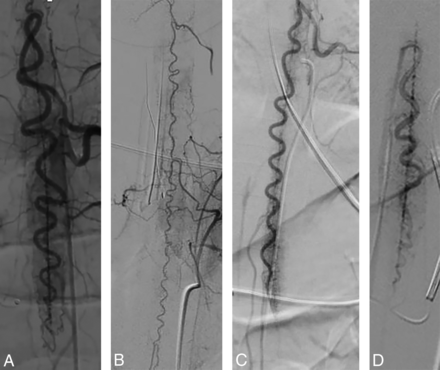

The results of catheter-directed spinal DSA are detailed in the Online Supplemental Data and highlighted in Fig 3. In all patients, catheter-directed DSA showed marked ectasia and tortuosity of the anterior spinal artery. In 3 of 4 patients, DSA of the dominant lower thoracic RMA showed the descending ramus of the anterior spinal artery to be much larger than the ascending ramus. Multiple RMAs were markedly ectatic in each patient, though the dominant lower thoracic RMA was most ectatic. In every patient, the central sulcal penetrators were markedly enlarged, producing a conspicuous pattern resembling the steps of a spiral staircase cycling between “on end” and “elongated” orientations in frontal-projection angiograms (Fig 3). By comparison, the posterolateral spinal arteries and radiculopial arteries were only modestly enlarged. Extrinsic spinal cord veins were modestly enlarged. Intrinsic spinal cord veins were not demonstrably enlarged. All patients demonstrated spinal cord hyperemia with brisk parenchymal venous drainage. In all patients, the prompt and diffuse angiographic appearance of the medullary and perimedullary veins followed the angiographic appearance of a hyperemic spinal cord parenchymal blush. There was no angiographic documentation of direct arterial-to-venous shunting (ie, AVF or AVM) in any patient.

Catheter-directed angiography findings. A, Frontal projection of a left T11 posterior intercostal artery angiogram in the early arterial phase from patient 1 shows marked ectasia of the dominant lower thoracic RMA and descending ramus of the anterior spinal artery (ASA). The ascending ramus of the ASA is mildly enlarged. The left posterolateral spinal artery is mildly enlarged. There is a uniform, unusually intense parenchymal capillary blush and early appearance of parenchymal draining veins. Note striking ectasia of the central sulcal penetrators. B, Frontal projection of a left supreme intercostal artery angiogram in the early arterial phase from patient 4 shows moderate diffuse ectasia of the ASA and central sulcal penetrators. Two RMAs are shown to be moderately ectatic. Note patchy intensification of the parenchymal capillary blush. C, Frontal projection of left posterior intercostal artery angiogram in the early arterial phase from patient 3 shows marked ectasia of the dominant lower thoracic RMA and descending ramus of the ASA. There is striking ectasia of the central sulcal penetrators. There is a uniform, unusually intense parenchymal capillary blush most prominent in the region of the conus medullaris and early appearance of parenchymal draining veins. D, Frontal projection of the right posterior intercostal artery angiogram in the early arterial phase from patient 2 shows ectasia of the dominant lower thoracic RMA and descending ramus of the ASA. Note striking ectasia of central sulcal penetrators.